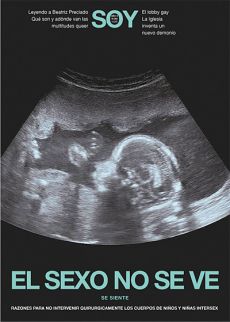

RAZONES PARA NO INTERVENIR QUIRURGICAMENTE LOS CUERPOS DE NIÑOS Y NIÑAS INTERSEX.